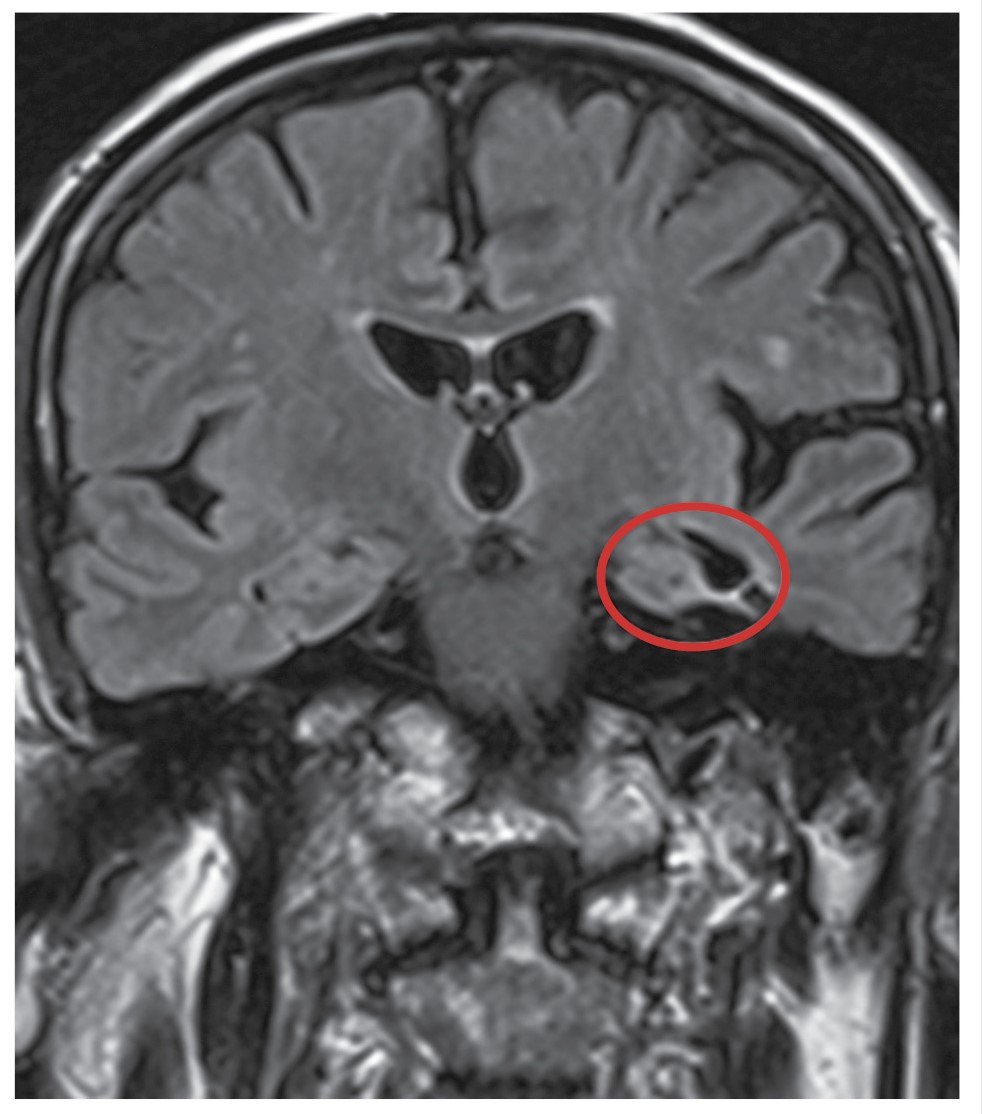

Гипоксические/ишемические процессы, возникающие в результате нарушения ЦП из-за низкого сердечного выброса и нарушения дыхания во сне, сопутствующих состояний, включая диабет и гипертонию, могут приводить к изменениям в скорлупе, мамиллярных телах, а также к локальным истончениям коры. Структурные аномалии ГМ, включая гиперинтенсивность БВ, атрофию МВД (гиппокампа), часто обнаруживают на МР-изображениях мозга как у бессимптомных, так и у пожилых людей с КН (рис. 2, 3).

Рис. 3. МР-томограмма ГМ, фронтальная проекция. МР-признаки атрофии МВД слева, хориоидальная щель расширена, толщина гиппокампа снижена.

Fig. 3. MR tomogram of the brain, frontal view. MR signs of atrophy of the medial temporal lobe on the left, the choroidal fissure is widened, the thickness of the hippocampus is reduced.